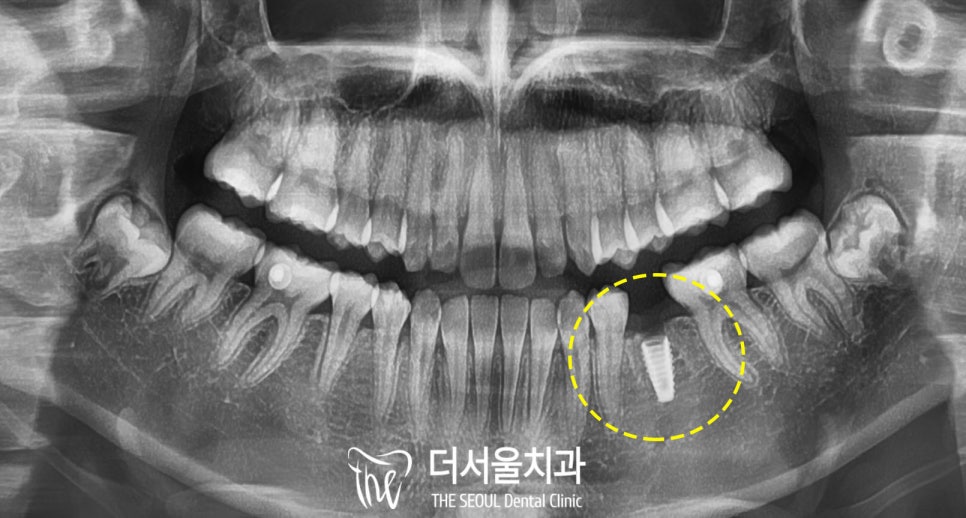

표시된 치아의

뿌리가 짧고 작은 것을 볼 수 있죠?

이를 무치증이라 부르며

28개 치아 중 1개 이상이

선천적으로 없는 경우입니다.

보통 아래 앞니,

아래 작은 어금니,

위 작은 어금니에서 주로 나타나며

종종 송곳니나 큰 어금니 쪽이

없는 경우도 있습니다.